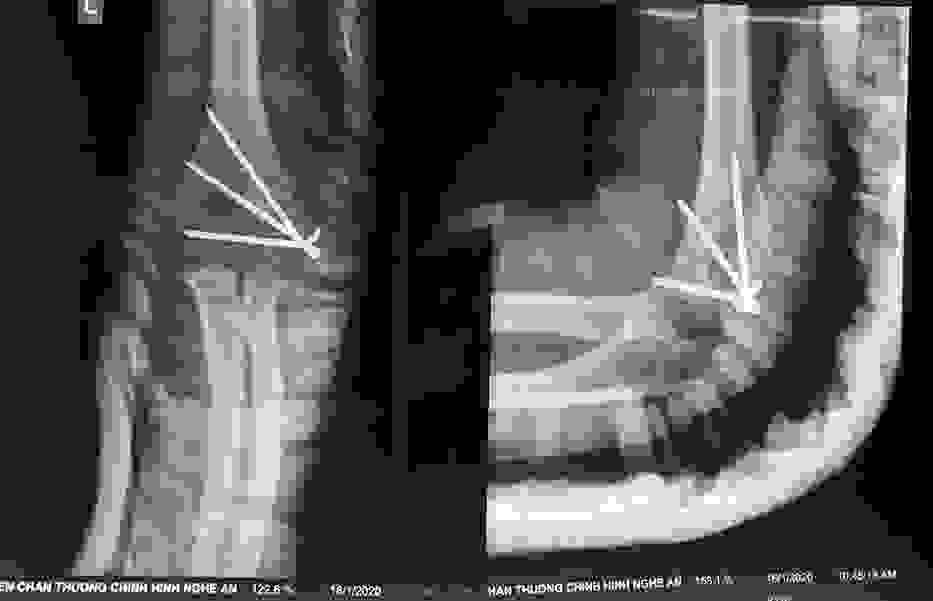

Phẫu thuật thành công ca bệnh hiếm gặp...khớp giả bẩm sinh xương chày

26/06/2019 17:00

Đã xem: 3526

Bệnh viện Chấn thương- Chỉnh hình Nghệ An, vừa phẫu thuật thành công cho bệnh nhi khớp giả bẩm sinh xương chày